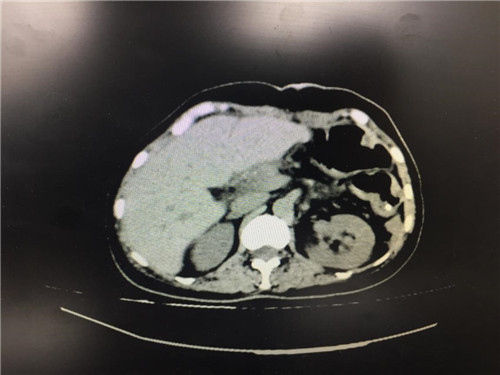

2月12日,普外科收治了一名女性患者,该患者入院一个月前,无明显诱因出现上腹部疼痛不适,呈间断性,向腰背部放射,有恶心,无呕吐,近一个月体重下降了5kg。门诊查上腹部CT提示:胰颈部新生物并胰管扩张;副脾。

患者病情复杂,在潘承恩教授和全科医生的讨论下,结合检验及检查结果,术前胰腺颈体部肿瘤诊断明确,科室积极制定手术方案,详细向家属探明病情并取得合作。2月21日,由普外科史和平主任、梁鹏锋医师主刀,在王谦、李垚磊医师配合下,成功对该患者实施了剖腹探查、全胰腺切除、脾脏切除术。手术中发现,患者胰腺颈体部可触及一大小约4cm包块,胰头部质软,胰腺体尾部质硬,遂决定行胰腺颈体尾部切除及脾脏切除术。在胰腺近侧断端切取部分胰腺组织送术中快速冰冻,提示查见异型增生的胰腺腺泡样组织,联系病理科考虑癌细胞残留,术中向家属谈明病情并取得同意,遂行胰十二指肠切除术,手术顺利,术后生命体征平稳,并于术后第四日进行了复查CT结果良好。